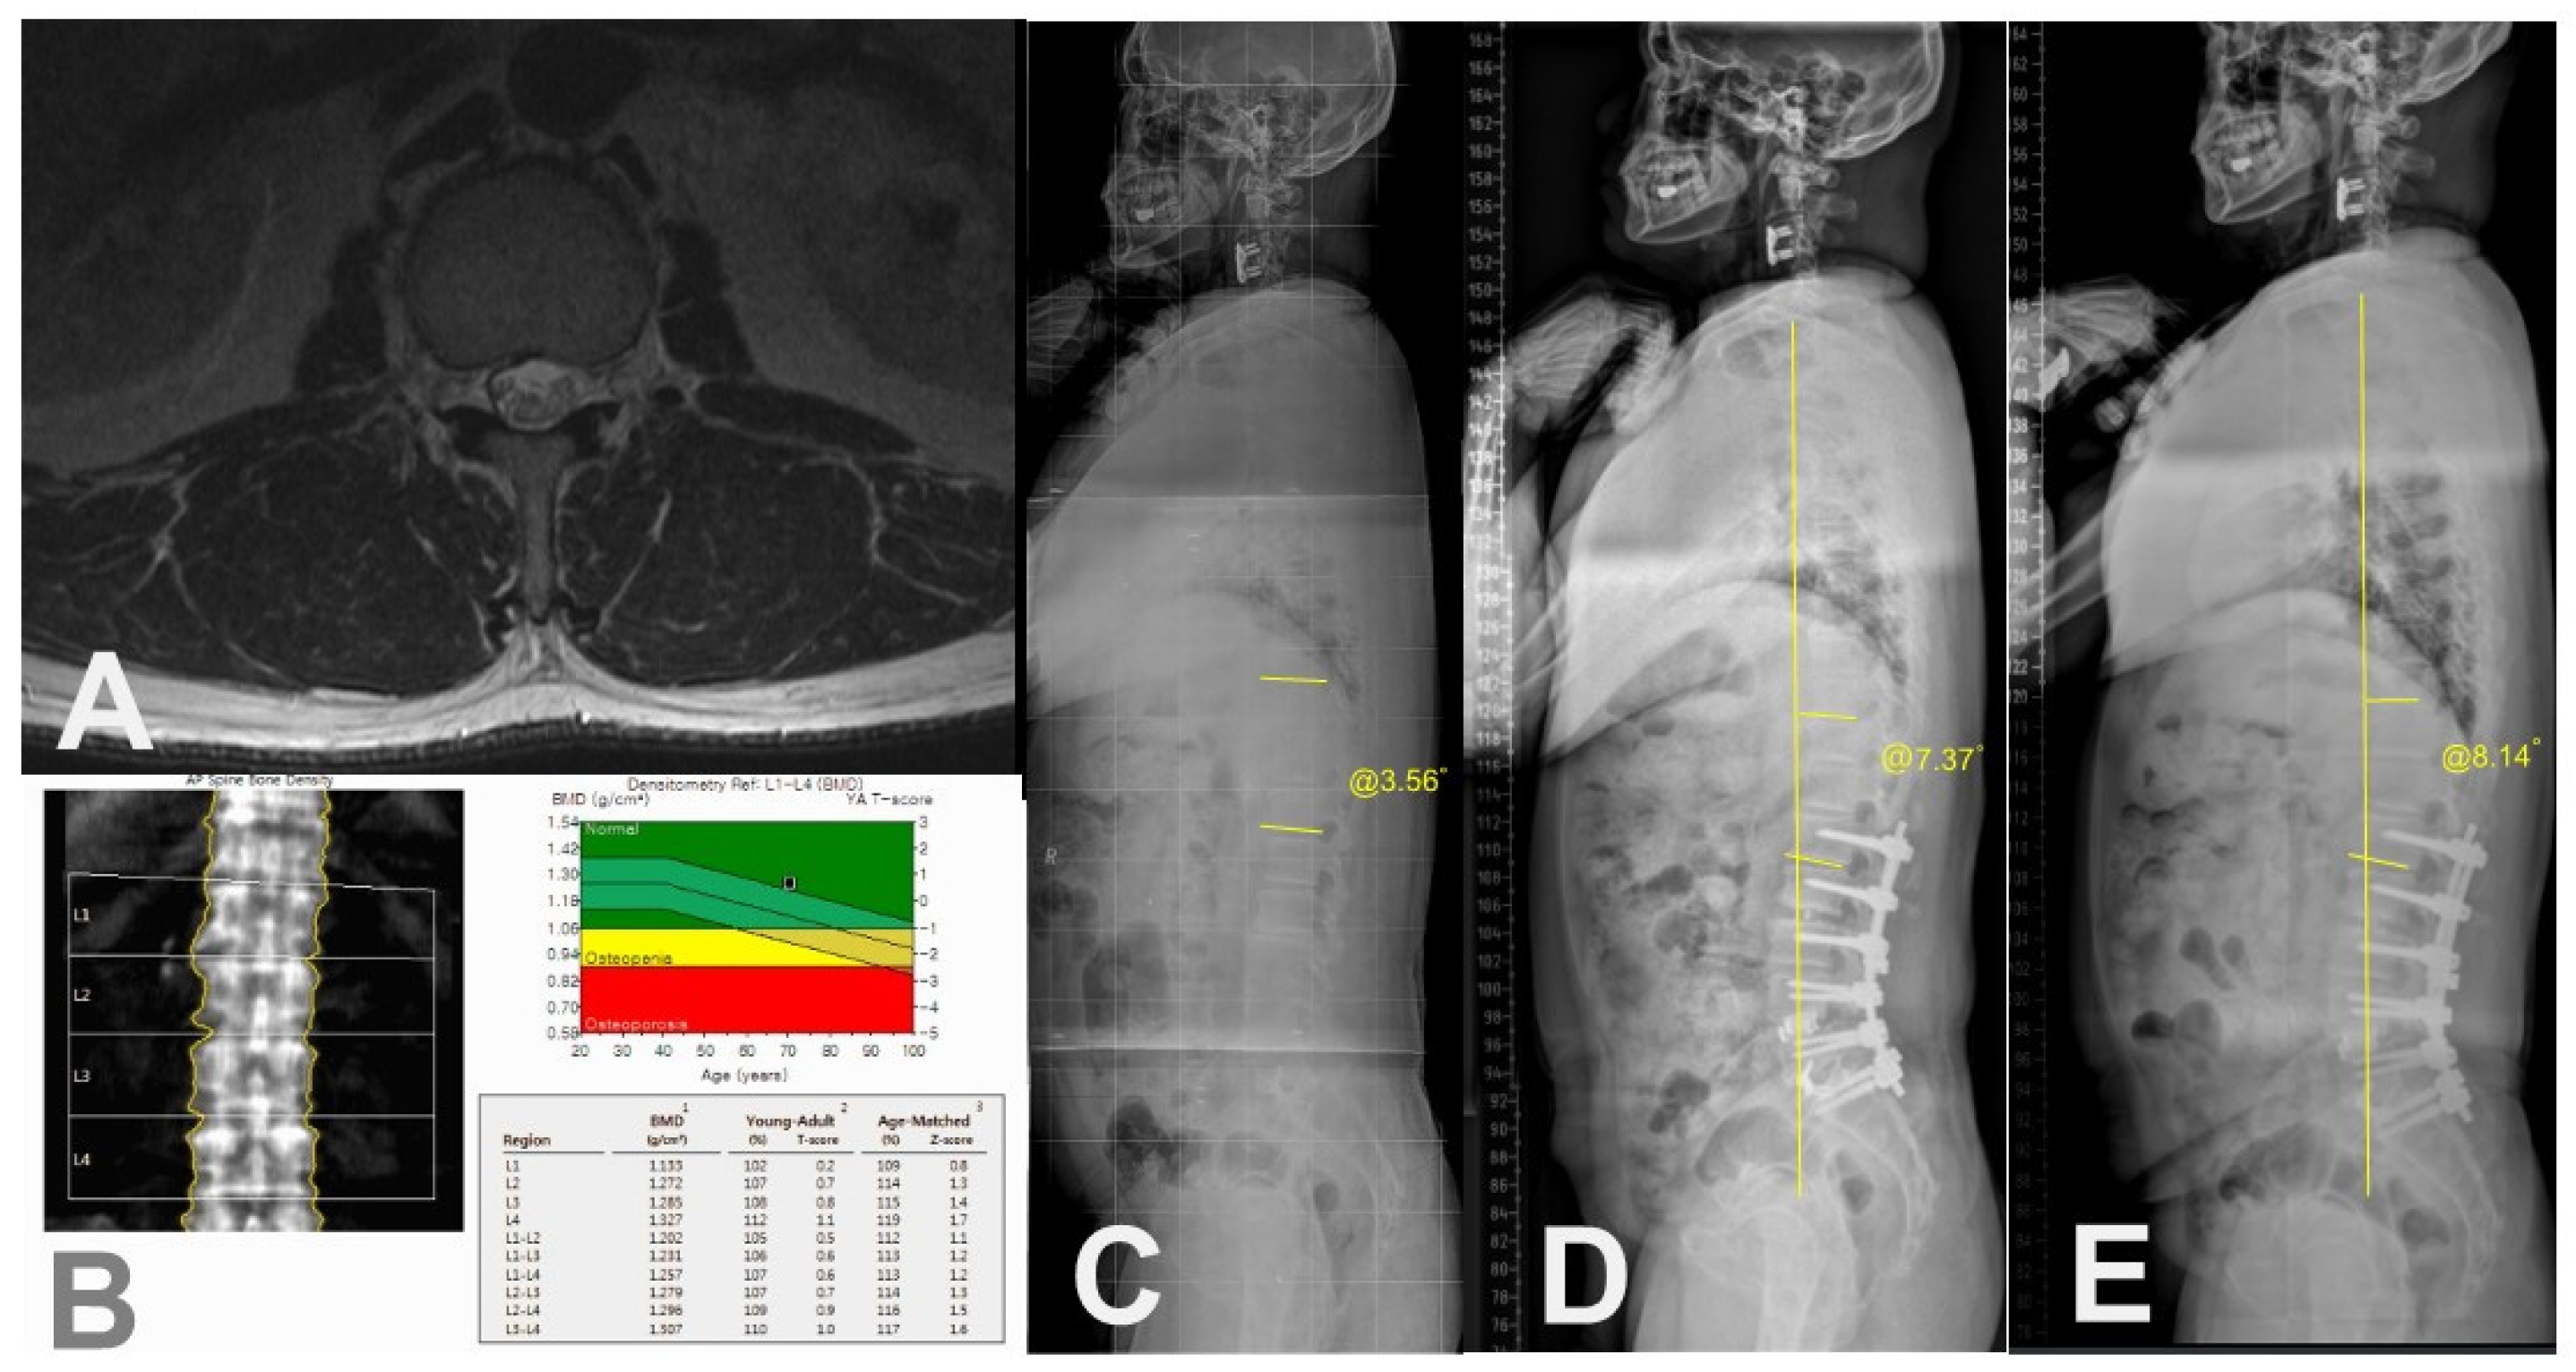

| BMD (T-score) | −1.8 ± 1.1 (range, −3.50–1.40) |

| Osteoporosis, n (%) | 18 (32.1) |

| BMD (T-score) | −2.4 ± 0.8 | −1.5 ± 1.1 | 0.006 * |

| Osteoporosis, n (%) | 14 (60.9) | 4 (12.1) | <0.001 * |

| Osteoporosis | 0.021 * | 20.50 | 1.59–264.99 |

| Muscle quality of T12-L1 (Fat infiltration in CSA of erector spinae) | 0.002 * | 43.60 | 4.11–463.06 |